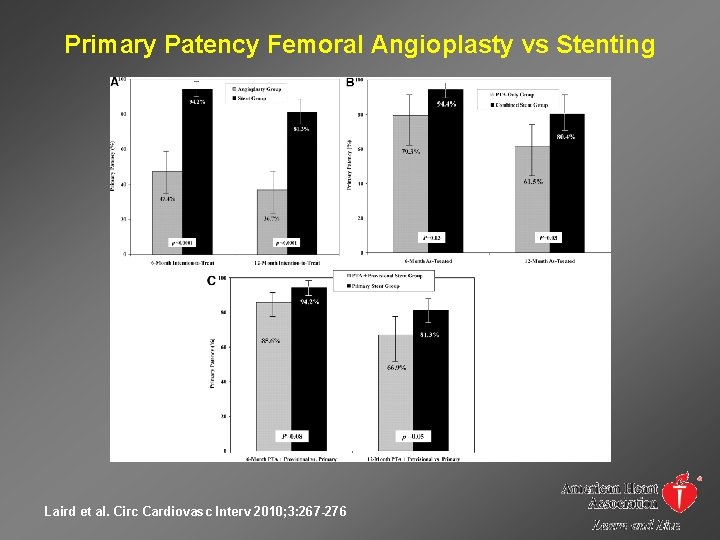

Primary Patency Femoral Angioplasty vs Stenting Laird et al. Circ Cardiovasc Interv 2010; 3: 267 -276